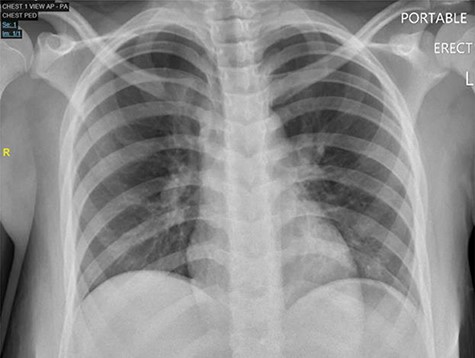

Case 2: A 13-year-old girl presented to the ED with a 3-day history of severe diffuse intermittent abdominal pain, worse in the periumbilical area, associated with nausea, vomiting and non-bloody diarrhea. No significant history was reported. On exam, the patient appeared sick, in acute distress, tachycardic and tachypneic with abdominal exam revealing diffuse tenderness with peritoneal signs. Laboratories showed normal WBC but lactic acidosis. Chest X-ray did not show free air under diaphragm (Fig. 3) and abdominal ultrasound showed moderate fluid in right upper quadrant of abdomen, for which CT of the abdomen and pelvis was ordered and it revealed free mesenteric fluid and extraluminal air in the pelvis suspicious for hollow viscus perforation (Fig. 4).

Chest X-ray PA, showing no cardiopulmonary disease, or free air under diaphragm.